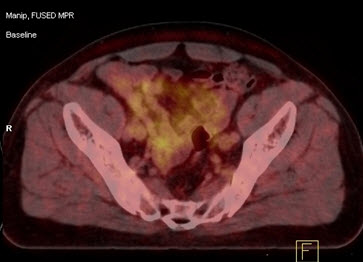

Hình 6. Bệnh nhân Vũ D.L., nam, 56 tuổi. Chẩn đoán: Non Hodgkin Lymphoma , GPB: WF7.Hình PET/CT trước và sau điều trị. Trước điều trị bệnh nhân có tổn thương hạch tại rất nhiều vị trí trong cơ thể: hạch cổ, hạch trung thất, hạch ổ bụng. Sau điều trị hóa chất 6 đợt, bệnh nhân được chụp PET/CT để đánh giá đáp ứng điều trị thấy các hạch hoàn toàn biến mất. Bệnh đáp ứng hoàn toàn.

Tin liên quan